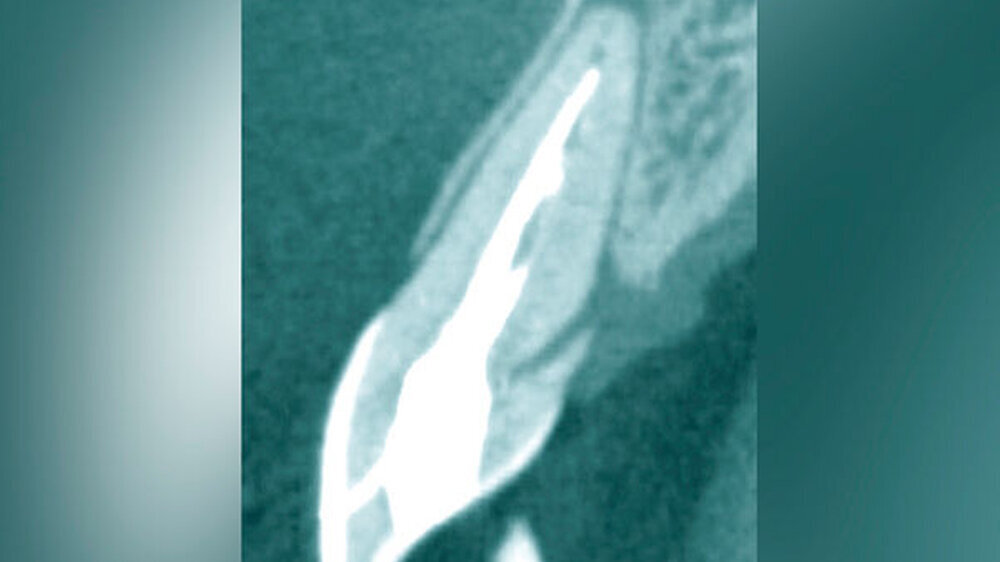

Eine weitere Möglichkeit, tief zerstörte Zähne möglichst schonend chirurgisch zu extrudieren, basiert auf axialen Zugsystemen (Abbildungen 2 bis 4). Diese erscheinen vorteilhaft bei sehr schwierigen Fällen, zum Beispiel bei Zähnen mit fehlendem Ansatzpunkt für die Zange sowie bei langen oder sehr ovalen Wurzeln. Axiale Zugsysteme ermöglichen die Übertragung von Zugkräften auf die Zahnwurzel, ohne die Alveole unnötig zu dehnen. Dazu wird eine spezielle Schraube in den Wurzelkanal eingebracht und das Gewinde der Schraube für eine ausreichende Friktion fingerfest eingedreht. An diese Schraube wird ein gerätespezifisches Zugsystem angelegt. Durch rein axial wirkende Zugkräfte werden traumatische Effekte auf Knochen und Wurzeloberfläche während der Zahnmobilisation minimiert. Gegebenenfalls können feine Luxatoren vorsichtig unterstützend eingesetzt werden. Im Tiermodell wurde an extrahierten und wieder replantierten Zähnen mit ovalem Querschnitt gezeigt, dass der Verlust von Zementoblasten auf der Wurzeloberfläche geringer ist, wenn ein axiales Zugsystem anstatt einer Extraktionszange verwendet wird.